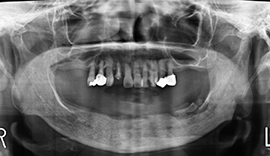

図❶ 初診時のパノラマX線写真

画像検査: パノラマX線写真にて、抜歯窩に腐骨様不透過像の分離を認める(図❶)。CTにて、抜歯窩相当部位に炎症性透過像と腐骨様不透過像の分離を認める(図❷)。